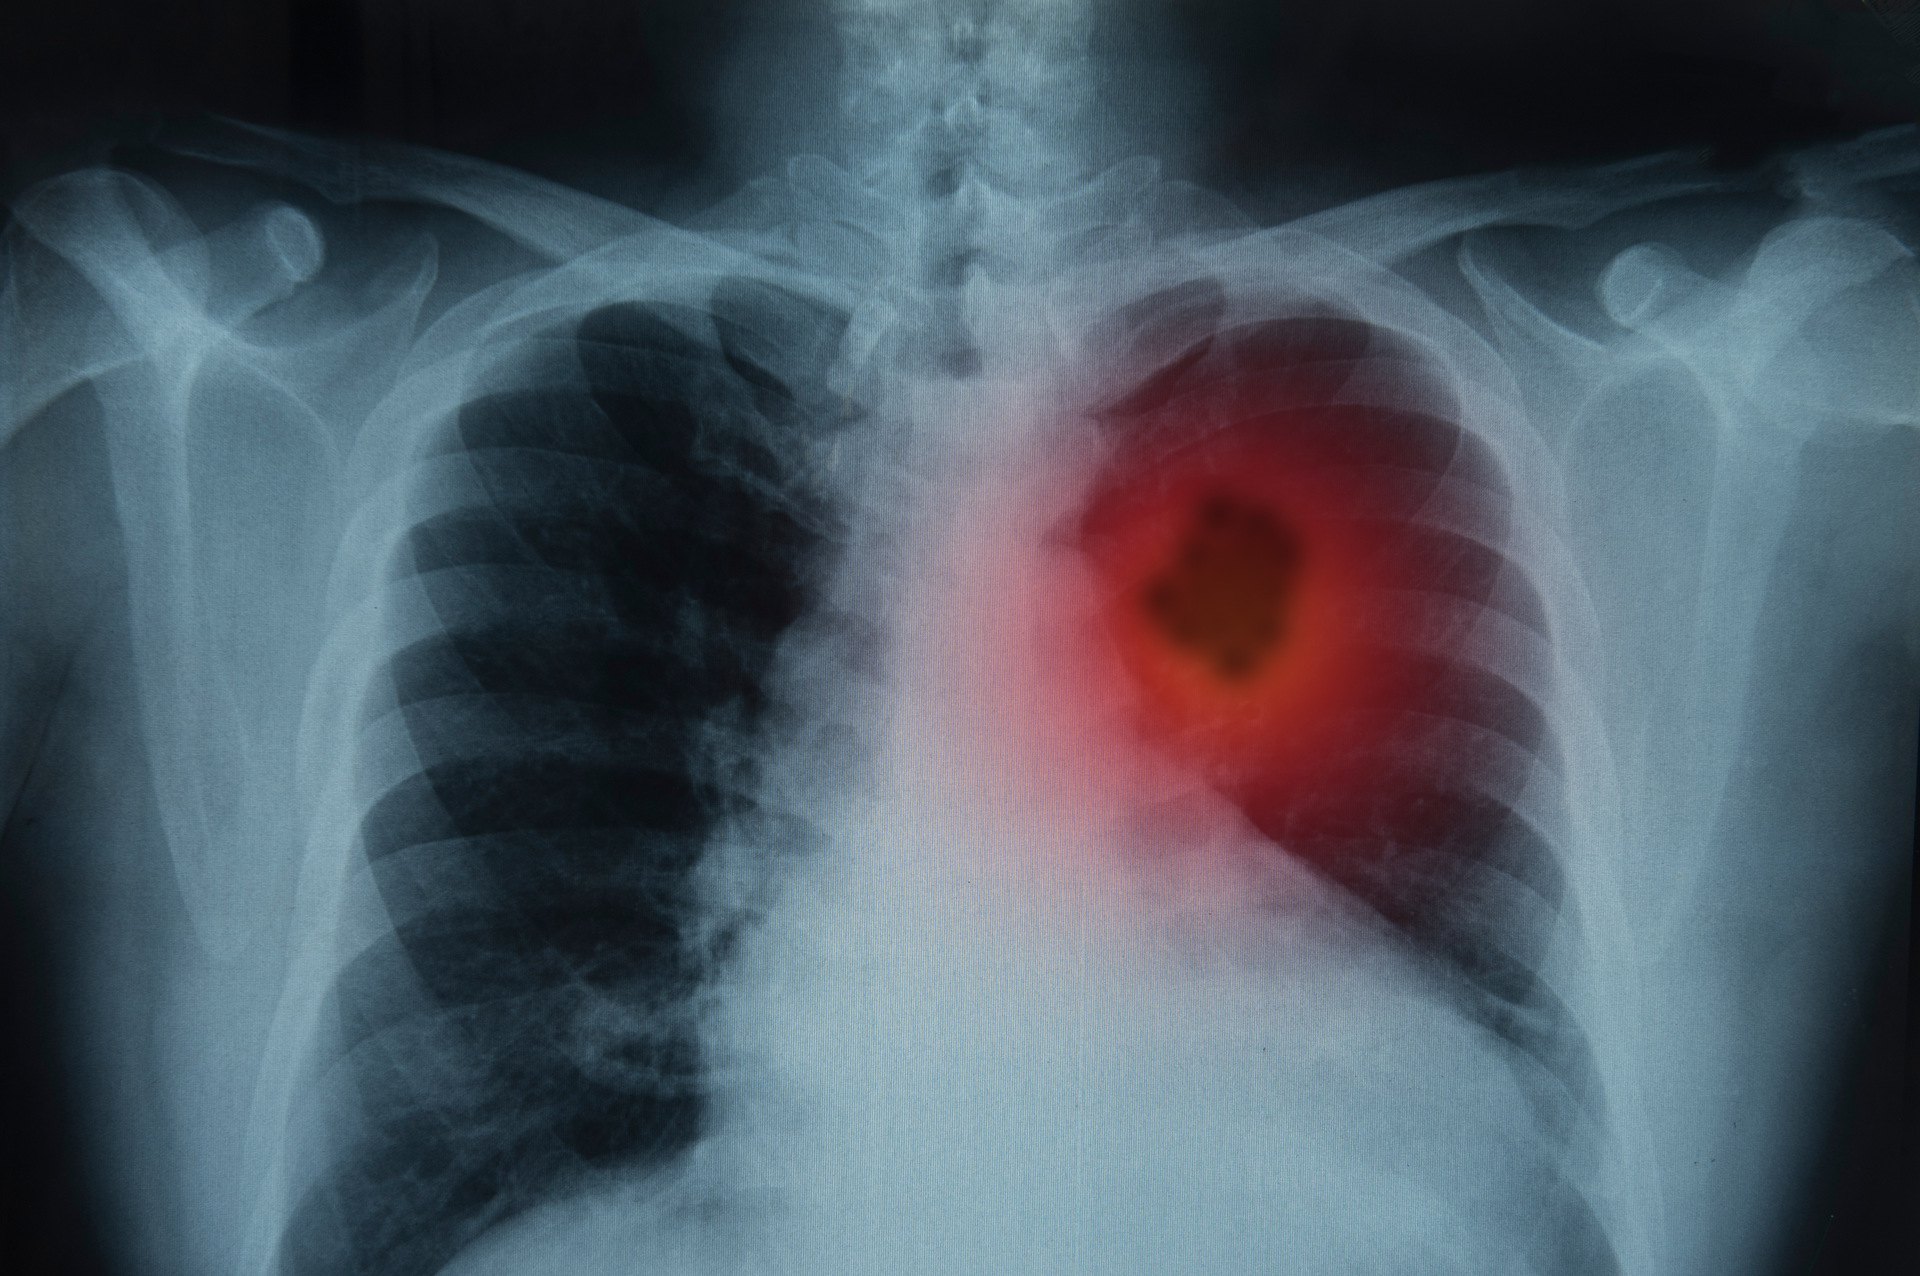

The National Cancer Institute, part of the National Institutes of Health (NIH), has helped launch a phase 3 randomized clinical trial of a two-drug combination to treat patients with advanced non-small cell lung cancer (NSCLC). Called the Pragmatica-Lung Study (or S2302), this is one of the first NCI-supported clinical trials to use a trial design that removes many of the barriers that prevent people from joining clinical trials. This “pragmatic” approach aims to increase accessibility to clinical trials.

The trial will evaluate whether a combination of two FDA-approved medications, ramucirumab (Cyramza, manufactured by Eli Lilly and Company) and pembrolizumab (Keytruda, manufactured by Merck), improves overall survival (how long people live) over standard treatment in people with advanced NSCLC whose disease has progressed after previous treatment with immunotherapy and chemotherapy.

The trial will enroll up to 700 participants from around the United States. Adults ages 18 and older with stage 4 or recurrent NSCLC who were previously treated with immune checkpoint inhibitors (a type of immunotherapy) and chemotherapy will be randomly assigned to receive either ramucirumab plus pembrolizumab or standard treatment. The study will look primarily at how long patients in the two groups live and is expected to complete enrollment by the end of 2025.